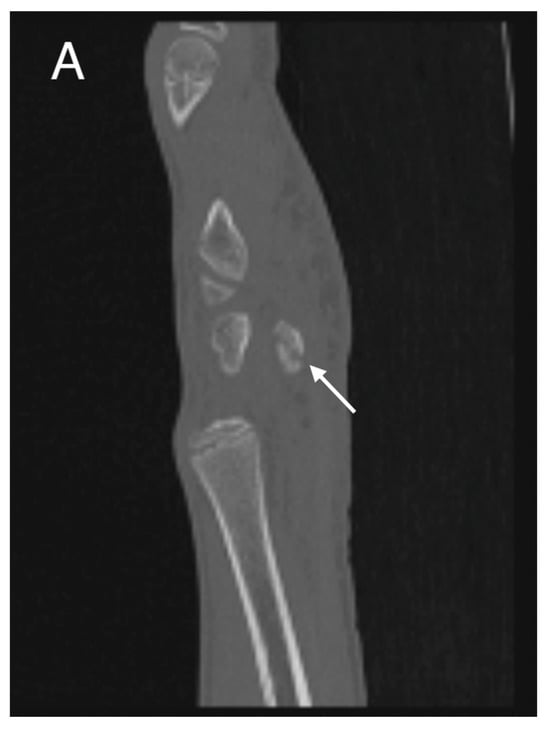

Initial conventional radiographic assessment showed no definitive fracture, with a potential suspicion of a proximal radius fracture (Figure 1). Due to significant tenderness over the radial fossa and pisiform, a CT scan was performed, confirming a nondisplaced scaphoid fracture and a suspected pisiform fracture with dislocation (Figure 2).

Figure 1.

Initial X-ray views in ap (left) and lateral (right) planes.